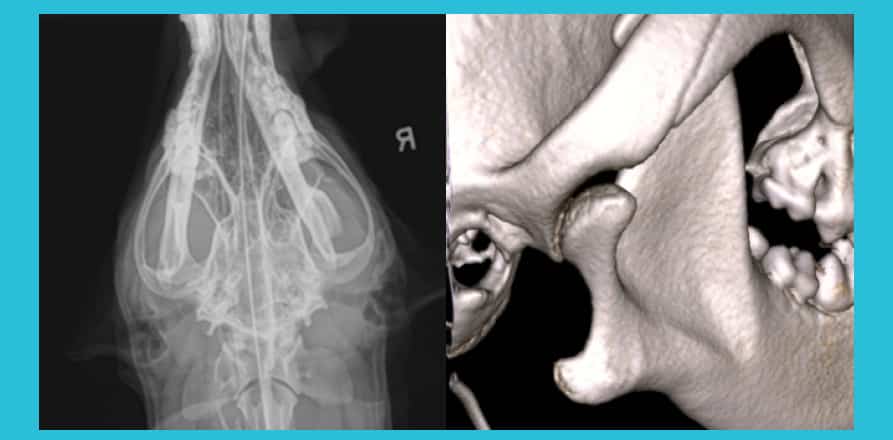

piper

By Xoran Marketing Case Studies Dental

27 Jan: 3D Visualization of Draining Tracts